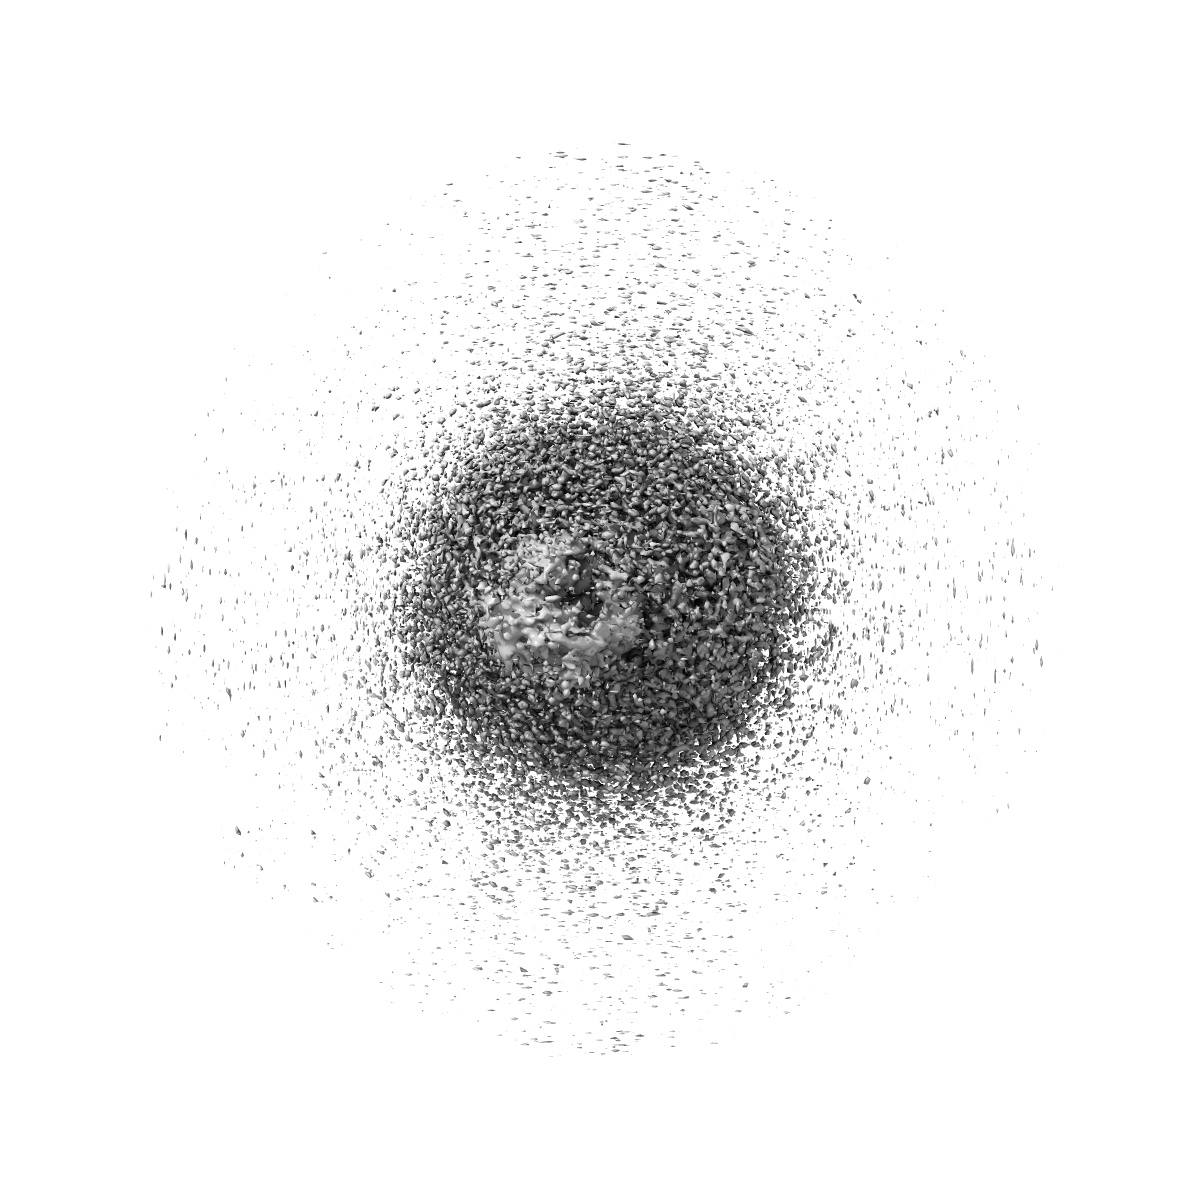

Cryo-EM structure of the retatrutide-bound human GCGR-Gs complex

Single-particle2.84 Å

Sample: Cryo-EM structure of the retatrutide-bound human GCGR-Gs complex